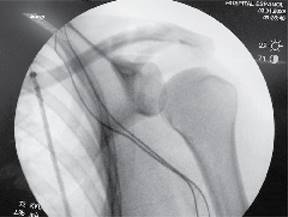

El injerto además de servir para la reconstrucción de los ligamentos CC, su interposición en el espacio AC funciona como espaciador, reemplazando la función del disco articular de dicha articulación. Se toma un control fluoroscópico en proyección anteroposterior, corroborando adecuada reducción de articulación AC (Figura 10). Se procede a irrigar herida quirúrgica con Microdacyn. Se cierra cuidadosamente la fascia deltotrapezoidea con puntos interrumpidos con sutura absorbible (Vicryl 2.0) y posteriormente por planos: tejido celular subcutáneo con sutura Vicryl 2.0 con puntos invertidos en «U» y piel con sutura Stratafix 3-0 con puntos continuos subdérmicos. Se inmoviliza extremidad torácica con inmovilizador de hombro y banda aductora.